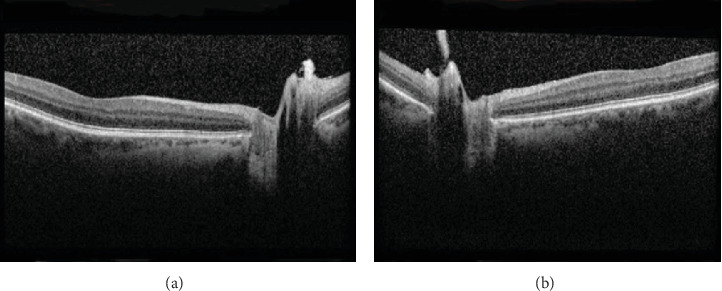

Purpose: The purpose of the study is to describe a case of vitreopapillary traction causing optic nerve head elevation. Observations: This case report describes a 64-year-old male who presented with left cloudy vision for 3 days. Dilated fundus exam showed normal right optic nerve with glial tissue nasally and left optic nerve head elevation and peripapillary hemorrhages in the left eye. Magnetic resonance imaging of the brain and orbits, erythrocyte sedimentation rate, and C-reactive protein were normal. Optical coherence tomography showed bilateral dense vitreous adhesions to the optic disc nasally causing traction and optic nerve head elevation of the left eye. The patient was diagnosed with vitreopapillary traction causing optic nerve head elevation, and observation was recommended. Conclusions and Importance: This case highlights the importance of clinical examination and ancillary testing in differentiating etiologies of optic disc elevation.